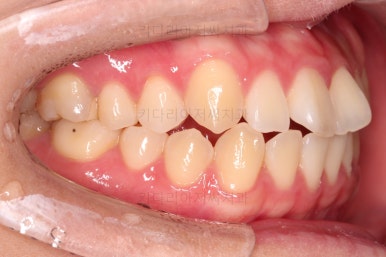

얼핏 보면 많이 삐뚤어지지는 않은 편인데, 눈에 바로 띄는 앞니가 뻗쳐 있으면서 획 돌아있는데요. 정렬이 필요한 상황이었습니다.

어금니쪽은 많이 삐뚠 편은 아니었으며, 윗니 앞니가 많이 앞으로 뻗쳐 있는 상태였습니다.

아까 말씀 드렸던, 왜 윗니 앞니만 뻗칠까?에 대한 대답은 "주걱턱의 골격구조를 가지셔서" 입니다.

아래턱이 앞으로 나오면 나올수록 윗니는 앞에 있는 아래턱과 만나기 위해 앞으로 뻗치는거죠.